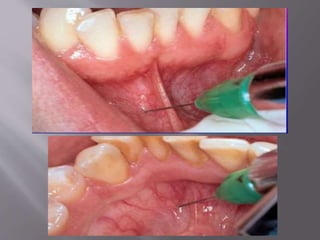

 Direct/ lateralwindow technique:  Sinus membrane is directly visualised by and instrumented by window created at the lateral wall of maxillary sinus

 Indirect/ osteotometechnique/ crestal approach/ transalveolar approach It is indicated when residual bone height is greater than or equal to 6mm